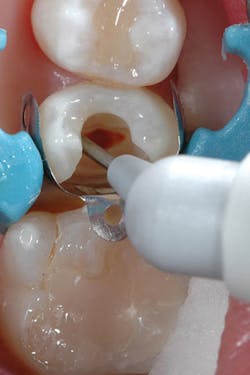

Although the bulk-fill flowable can be placed in larger increments, a small increment was placed first to ensure sufficient curing of the material at the floor of the chamber (figures 3 and 4). The next layer of SureFil SDR flow+ was placed in a 4-mm bulk increment again, followed by 20 seconds of light curing. A final layer of universal composite was placed, occlusion was checked, and after a final polish and postoperative radiograph, the patient was released (figures 5 and 6).